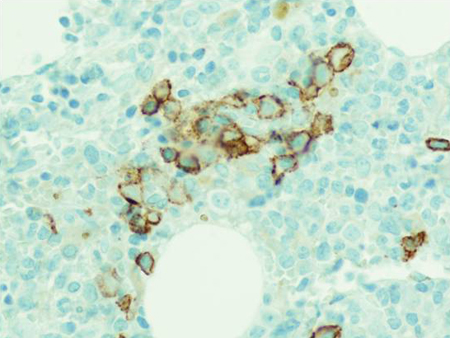

[Figure caption and citation for the preceding image starts]: CD138 immuno-histochemical staining highlighting small clusters of plasma cellsFrom the collection of Ola Landgren, MD, PhD [Citation ends].